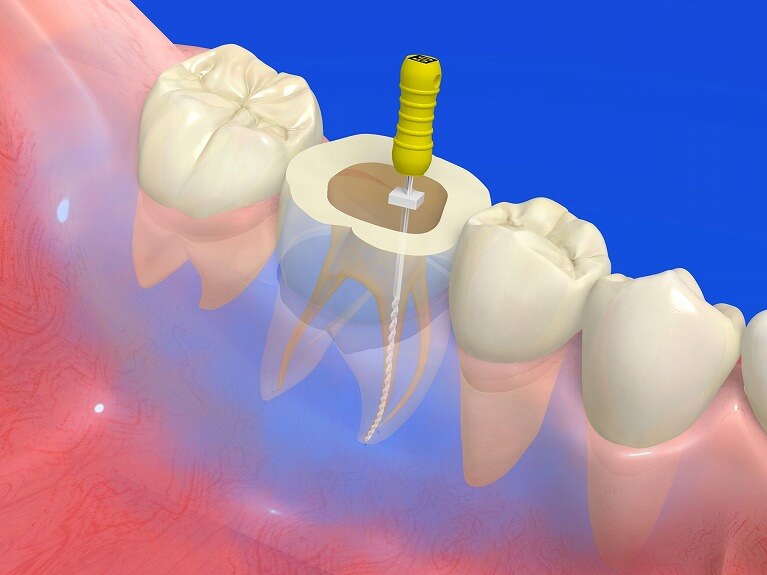

根管治療に欠かすことが出来ないマイクロスコープ

歯の根の中というのは細く、そして非常に複雑な構造をしており、肉眼では根管の奥まで確認することは不可能です。このような根管治療は歯科医師の経験や勘に頼る部分が多く、その不確実な要素の多さから、非常に難しい治療とされてきました。

歯の根の中というのは細く、そして非常に複雑な構造をしており、肉眼では根管の奥まで確認することは不可能です。このような根管治療は歯科医師の経験や勘に頼る部分が多く、その不確実な要素の多さから、非常に難しい治療とされてきました。

しかしながら、マイクロスコープが登場した現在では歯の根の奥まで確認することが可能となり、精度の高い、安全な根管治療を行うことが出来るようになっています。

しもやま歯科クリニックではマイクロスコープを導入し、徹底的に再発のリスクを抑えた根管治療を行っております。

現時点では、日本全国を探してみてもマイクロスコープを導入している歯科医院というのはごく僅かですが、当院では精度の高い、再発リスクの無い根管治療のためにはマイクロスコープは必要不可欠だと考えています。

根管治療の流れ